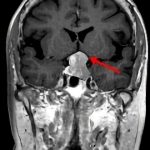

断層撮影